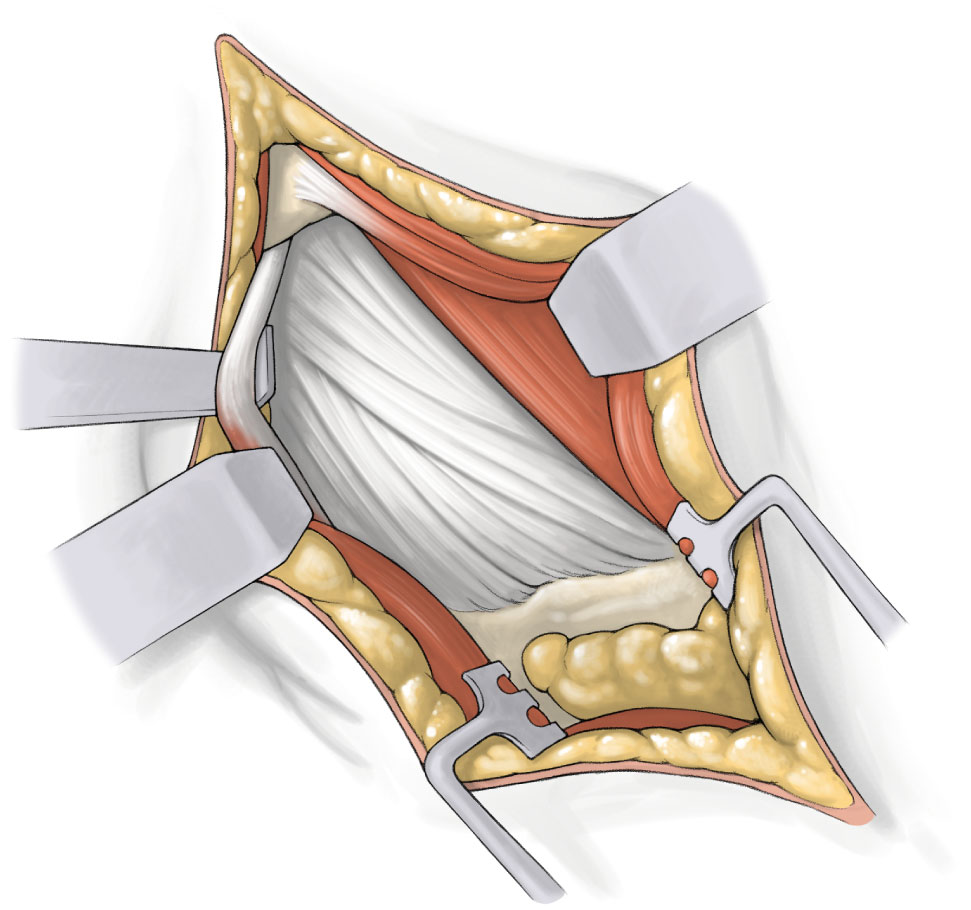

用一对带翼剥离器将臀大肌纤维纵向牵开,确保创伤最小,暴露臀中肌后缘的滑囊组织,在仔细切开非常薄的滑囊组织后,将骨膜剥离器至于臀中肌下方显露关节囊,随后用钝头Hohmann拉钩替换骨剥,轻压以维持拉钩在臀中、小肌之间的位置。髋关节外展、外旋,将Cobb至于梨状肌肌腱和臀小肌之间,随后用钝头Hohmann拉钩替换骨剥,此时放下膝关节,将下肢恢复到基础体位。

轻压以维持Hohmann拉钩维持其在后方关节囊和外旋肌之间的位置,如果梨状肌肌腱对拉钩产生较大的对抗,可以直视下对其进行松解。使用骨剥将臀小肌从前方推开,暴露关节囊,用电刀沿皮肤切口方向切开关节囊。使用长腿电刀切开粗隆筋膜,以避免股骨颈基底周围出血。关节囊切开范围从股骨颈鞍部延伸到髋臼近端1cm,剥离髋臼边缘的关节囊附着点,剥离范围向前、向后各延伸1cm。在此过程中可抬高膝关节以降低外旋肌群的张力。钝头Hohmann拉钩置于关节囊和股骨颈之间,放下膝关节,让下肢恢复基础体位,充分显露股骨大转子、股骨颈及头颈交界区。

将患肢恢复至初始体位,准备处理髋臼侧。在髋臼的前方、后方,以两把带尖Hohmann置于关节囊和盂唇之间的髋臼窝中,切除盂唇和钙化组织,在切口近端髋臼边缘的关节囊下放置一个Zelpi牵开器,切口远端放置一个Romanelli牵开器,形成髋臼锉进入髋臼的通道,移除尖头Hohmann拉钩,用直角骨钩勾住髓腔锉,将股骨近端向前拉。